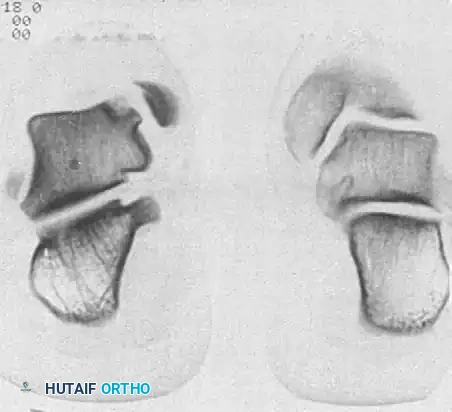

Radiographs of a stage III lateral lesion. (A) Preoperative radiograph showing a detached but undisplaced fragment. (B) Postoperative resolution following excision.

Early evidence of OLT in a child with open physes (A), demonstrating consolidation after 6 months of conservative management (B).